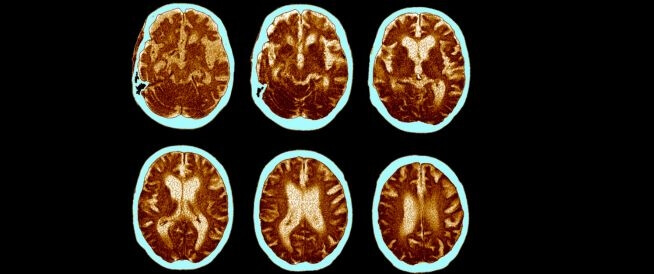

وجدت دراسة جديدة بقيادة باحثين من جامعة كاليفورنيا لوس أنجلوس أن نوعًا معينًا من خلايا الجهاز المناعي، وهي الخلايا التائية CD8، قد تلعب دورًا في مرض ألزهايمر، إليك التفاصيل.

نجح الفريق البحثي الذي يضم الدكتورة ياماكاوا والدكتورة جيسيكا ريكساش لأول مرة في إظهار أنّ أحد أنواع الخلايا المناعية - وهي الخلايا التائية القاتلة (CD8) - كانت مرتفعة باستمرار في أدمغة البشر المصابين بالزهايمر.

كانت الأبحاث السابقة على الفئران والسائل النخاعي للإنسان قد أشارت إلى احتمالية وجود ارتفاع لخلايا المناعة التائية في أدمغة مرضى ألزهايمر. لكن هذه الدراسة الجديدة هي الأولى التي تُثبت فعلياً وجود هذه الخلايا بكميات كبيرة في عينات من أدمغة بشرية مصابة بالمرض.

وأشارت الدراسة أيضًا إلى أنّ هذه الخلايا تفاعلت مع الخلايا الدبقية الصغيرة، وهي نوع آخر من خلايا الجهاز المناعي الموجودة في الدماغ، التي ترتبط ببروتين بيتا أميلويد، الذي يعتبر المكون الأساسي لـ"لويحات الأميلويد" في أنسجة الدماغ؛ العلامة المميزة لمرضى الزهايمر التي تضعف اتصال الخلايا العصبية ببعضها.